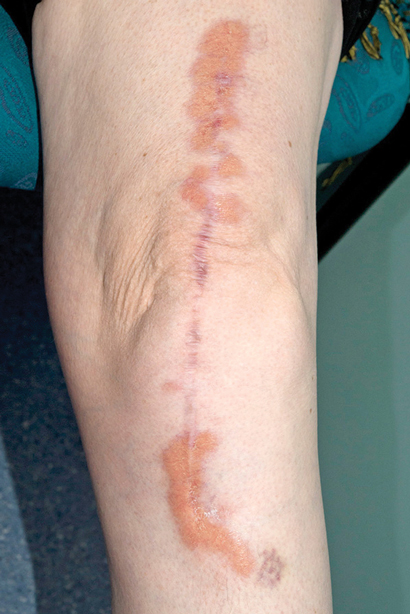

Further assessment found no risk factors for tuberculosis exposure and no symptoms of underlying infection. Dermatology consultation was requested and the skin nodules were closely examined. These included a 1 × 2 cm violaceous nodule on the left side of the woman's neck, a 2 × 5 cm yellowish plaque on her left flank, and a large violaceous-yellow plaque exhibiting Koebner phenomenon along the scar from her left total knee replacement surgery (Box 2). The patient reported that they had been present for 8–12 months and were asymptomatic. Biopsy specimens from the lesions on her neck and flank showed identical histological features to the liver specimen, again negative for Mycobacterium tuberculosis on Ziehl–Neelsen stain, culture and polymerase chain reaction (PCR) testing. A previous biopsy sample of the plaque overlying her knee-replacement scar had been taken by a dermatologist and showed non-discrete granulomatous inflammation and necrobiosis (Box 3, A). In retrospect, this was consistent with her current skin sample.